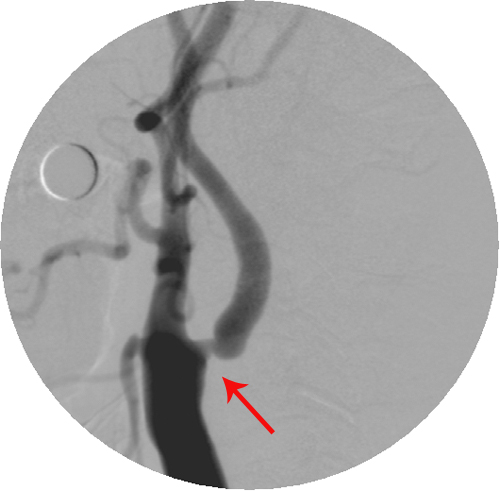

脑血管造影(广水市第一人民医院):右侧颈内动脉起始段重度狭窄,左侧颈内动脉起始段轻度狭窄。

颈动脉彩超(湖北省中山医院):双侧颈动脉内中膜增厚伴多发斑块形成;右侧颈内动脉起始段狭窄(50-69%)。

该患者反复头晕不适实为TIA发作,颈动脉超声及脑血管造影证实其右侧颈内动脉起始段存在重度狭窄,符合CEA手术指征。手术可有效预防中风发作。